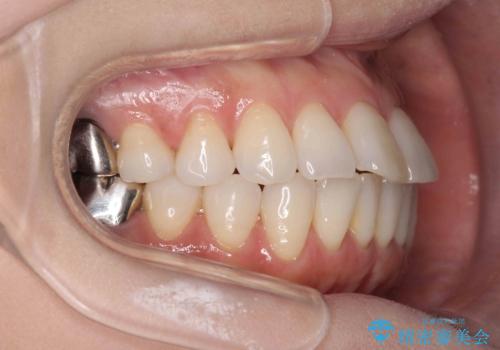

抜歯をせず前歯の角度を改善するマウスピース矯正治療

- 突き出た前歯の角度を改善したい、と矯正治療を希望され来院されました。

抜歯を行いワイヤー矯正で2-3年程度の時間をかけて、しっかり前歯を後方に移動させるか、

抜歯を行わずにIPR(歯の間に空隙を設ける)で可及的に角度の改善を行うか、

2通りの治療方針をご提案しました。

治療期間が約半年で行うことができ、歯を抜かずにマウスピース矯正で可及的に前歯の角度を改善する治療方針を

奥歯の状態等も鑑みて選択されました。

約半年で大きく前歯の角度を改善することができ、抜歯を行わない矯正治療の結果に大変喜んでいただくことができました。